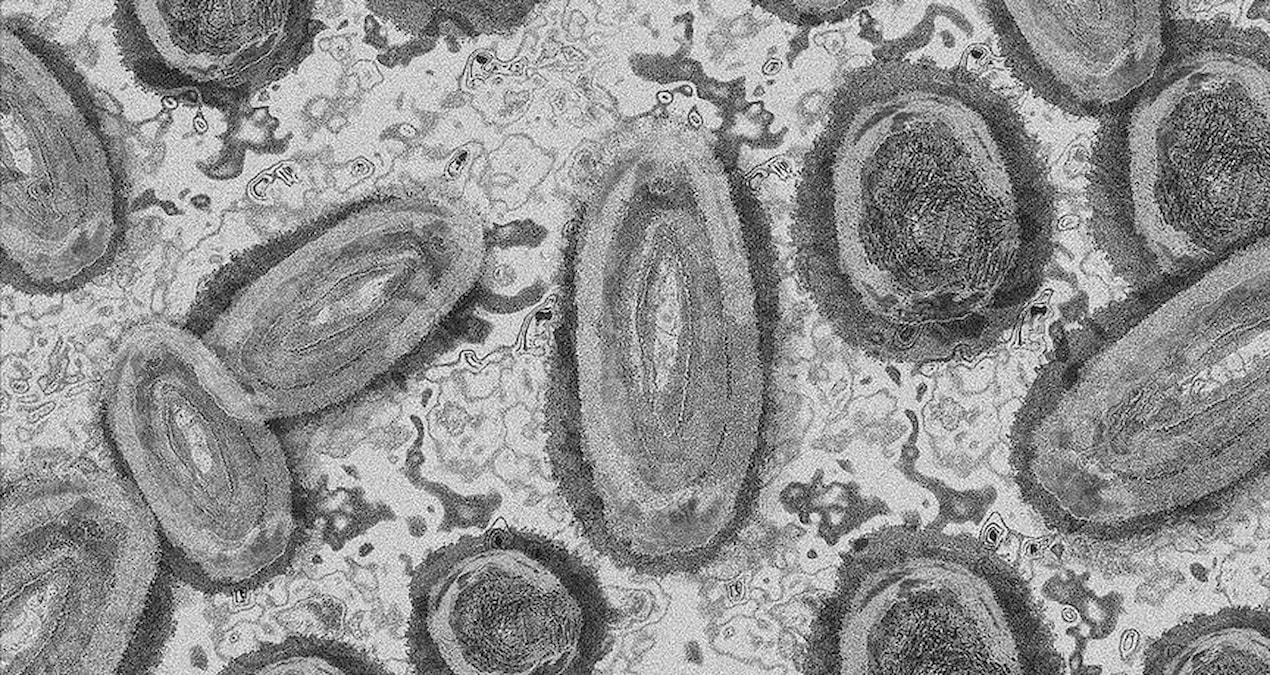

Avrupa ve Amerika ülkelerinde artış gösteren kuş gribi vakalarının Türkiye'de de görülmesinin ardından Yumurta Üreticileri Merkez Birliği Başkanı ve Beyaz Et Sanayicileri ve Damızlıkçıları Birliği Derneği Başkanı konuya ilişkin açıklamalarda bulundu. Tarım ve Orman Bakanlığı'ndan yapılan açıklamada, Konya'nın Meram ilçesinde...